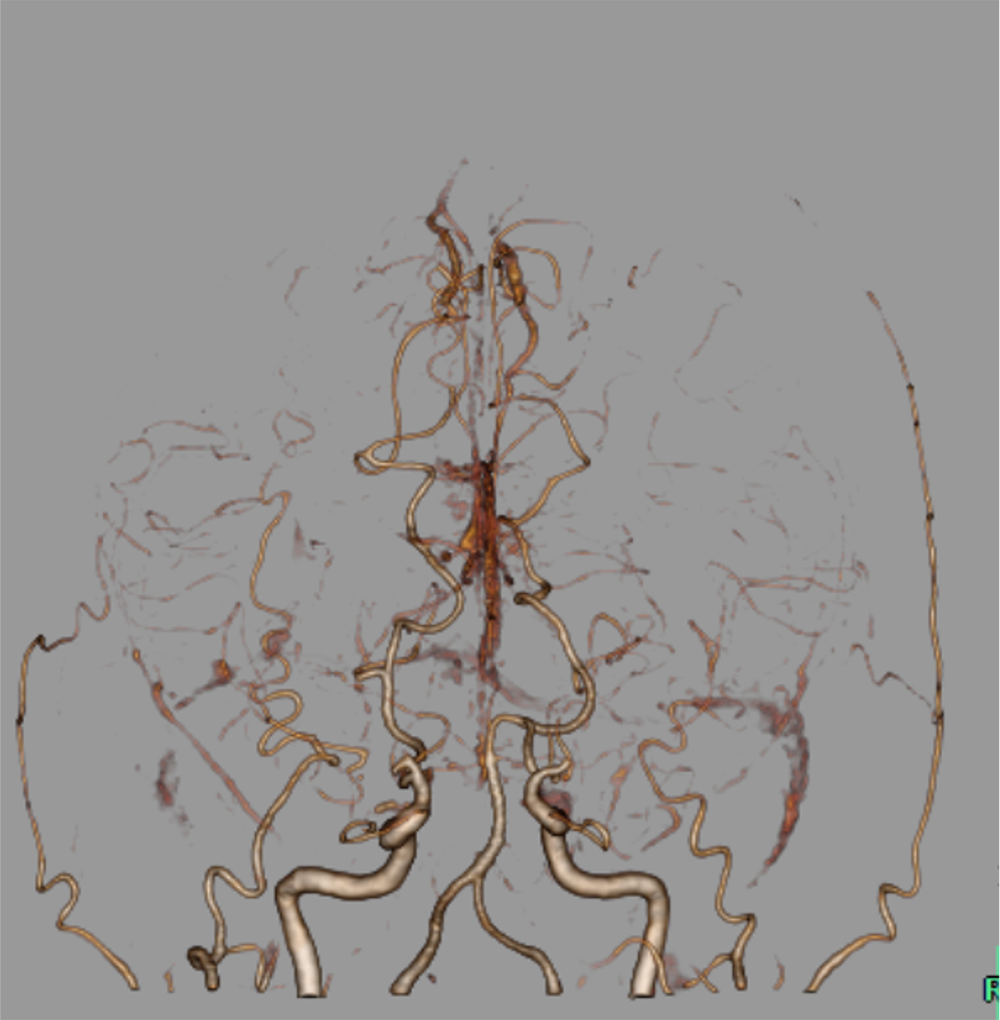

14歳ごろから手足の痺れやめまいなどを自覚しており、兄弟のもやもや病による脳卒中を契機にMRI撮像され、もやもや病と診断された。CTAで両側内頸動脈は閉塞しており、周囲に微細な増生血管をみとめた。前大脳動脈や中大脳動脈は狭窄しており、両側後大脳動脈に拡張を認めた。脳血流SPECTで左前頭葉、側頭葉に血流低下を認め、間接的血行再建術が施行された。

もやもや病における新生血管(もやもや血管)は血管径が細く、通常の撮影では明瞭な描出が難しいことがある。100kVの低管電圧撮影を用いることでもやもや血管の微細なネットワークを鮮明に描出し、病状評価や治療計画立案に役立てている。

血行再建術では、STA-MCAを直接吻合する方法のほか、STA、DTA、MMAなどを脳表と接続する間接血行再建術も広く施行されており、末梢の微細な血管解剖の取得までもが必要となる。

CT技術や撮像プロトコル設定について